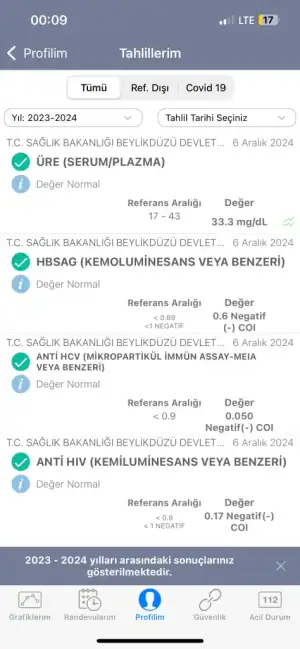

Merhaba bugün kadın hastalıkları ve doğum bölümüne gittim rahim ağzında yara var diye ve bana yakma önerdiler bi kaç test yaptılar anestezi için ve sonuçları pazartesi göstericem ama sonuçlar çıktığı için merak ediyorum aranızda anlayan veya doktor olan biri varsa cevaplayabilirmi rica etsem?

IMG_8035.webp32,3 KB · Görüntüleme: 115

IMG_8035.webp32,3 KB · Görüntüleme: 115 -

IMG_8036.webp32,2 KB · Görüntüleme: 112

IMG_8036.webp32,2 KB · Görüntüleme: 112 -

IMG_8037.webp20,9 KB · Görüntüleme: 115

IMG_8037.webp20,9 KB · Görüntüleme: 115 -

IMG_8038.webp21,8 KB · Görüntüleme: 104

IMG_8038.webp21,8 KB · Görüntüleme: 104 -

IMG_8039.webp21,3 KB · Görüntüleme: 108

IMG_8039.webp21,3 KB · Görüntüleme: 108 -

IMG_8040.webp18 KB · Görüntüleme: 105

IMG_8040.webp18 KB · Görüntüleme: 105 -

IMG_8041.webp20,9 KB · Görüntüleme: 101

IMG_8041.webp20,9 KB · Görüntüleme: 101 -

IMG_8042.webp40,6 KB · Görüntüleme: 115

IMG_8042.webp40,6 KB · Görüntüleme: 115